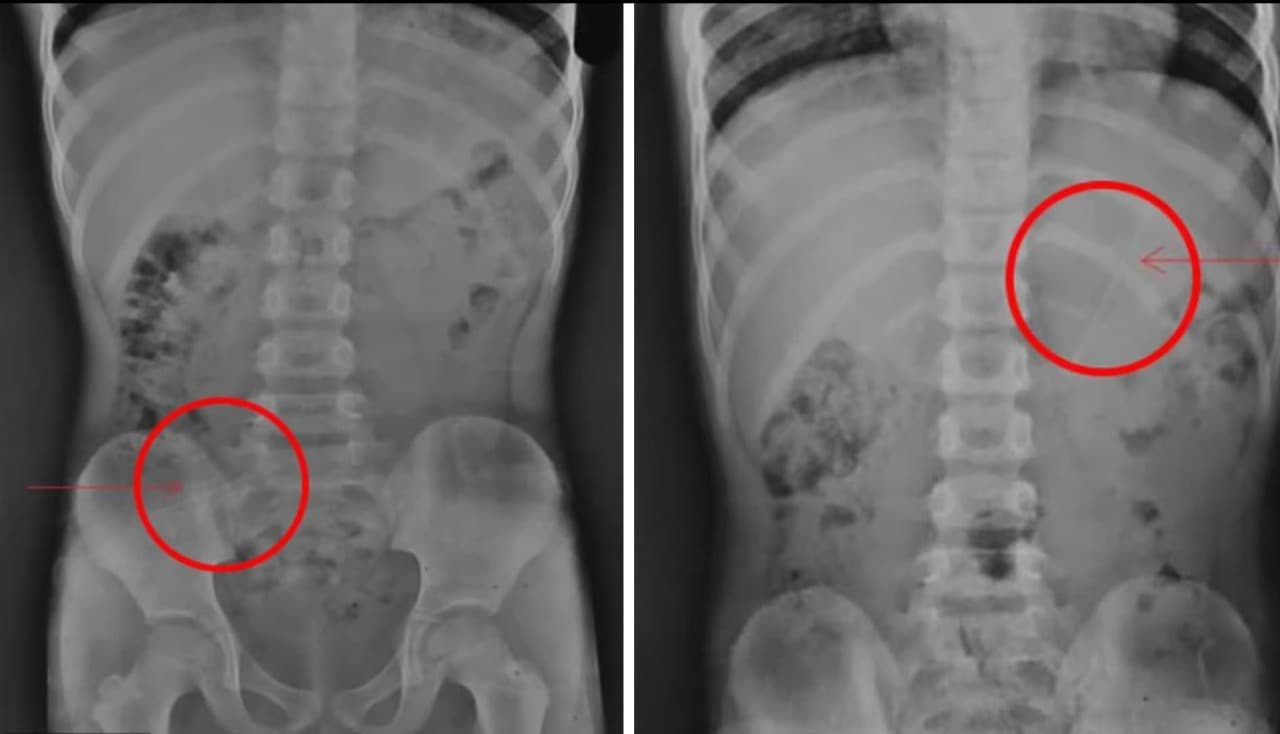

. As imagens do tórax e abdômen mostraram que o lápis estava no estômago. (Foto: Reprodução/Radiolofy CaseReports)

O menino estava sendo acompanhado por médicos locais, após a criança relatar o acontecimento 4 horas depois. Os médicos fizeram diversas radiografias para saber onde o lápis estava e quais os possíveis riscos que ele corria. As imagens do tórax e abdômen mostraram que o lápis estava no estômago.